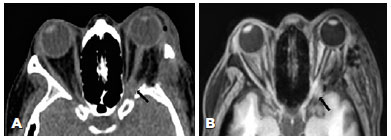

On postoperative day 1, she reported no light perception in the OD. Computed tomography (CT) and magnetic resonance imaging (MRI) performed on the same day revealed edema of the medial rectus muscle and apical hemorrhage involving the optic nerve canal (Figure 1). Vision restoration by enlarging the medial decompression was unsuccessful. After 2 years of follow-up, permanent right eye blindness ensued.

02-fig01.jpg)

To our knowledge, no study has reported vision loss caused by apical bleeding after orbital decompression, wherein a small volume of blood compresses the optic nerve on its entrance in the optic canal. With both MRI and CT, the blood present in the orbital apex caused blurring of the orbital fat between the optic nerve and the muscular cone. CT can distinguish blood from edema because blood has higher Hounsfield units (mean = 60) than fluid (mean = 0)(12).